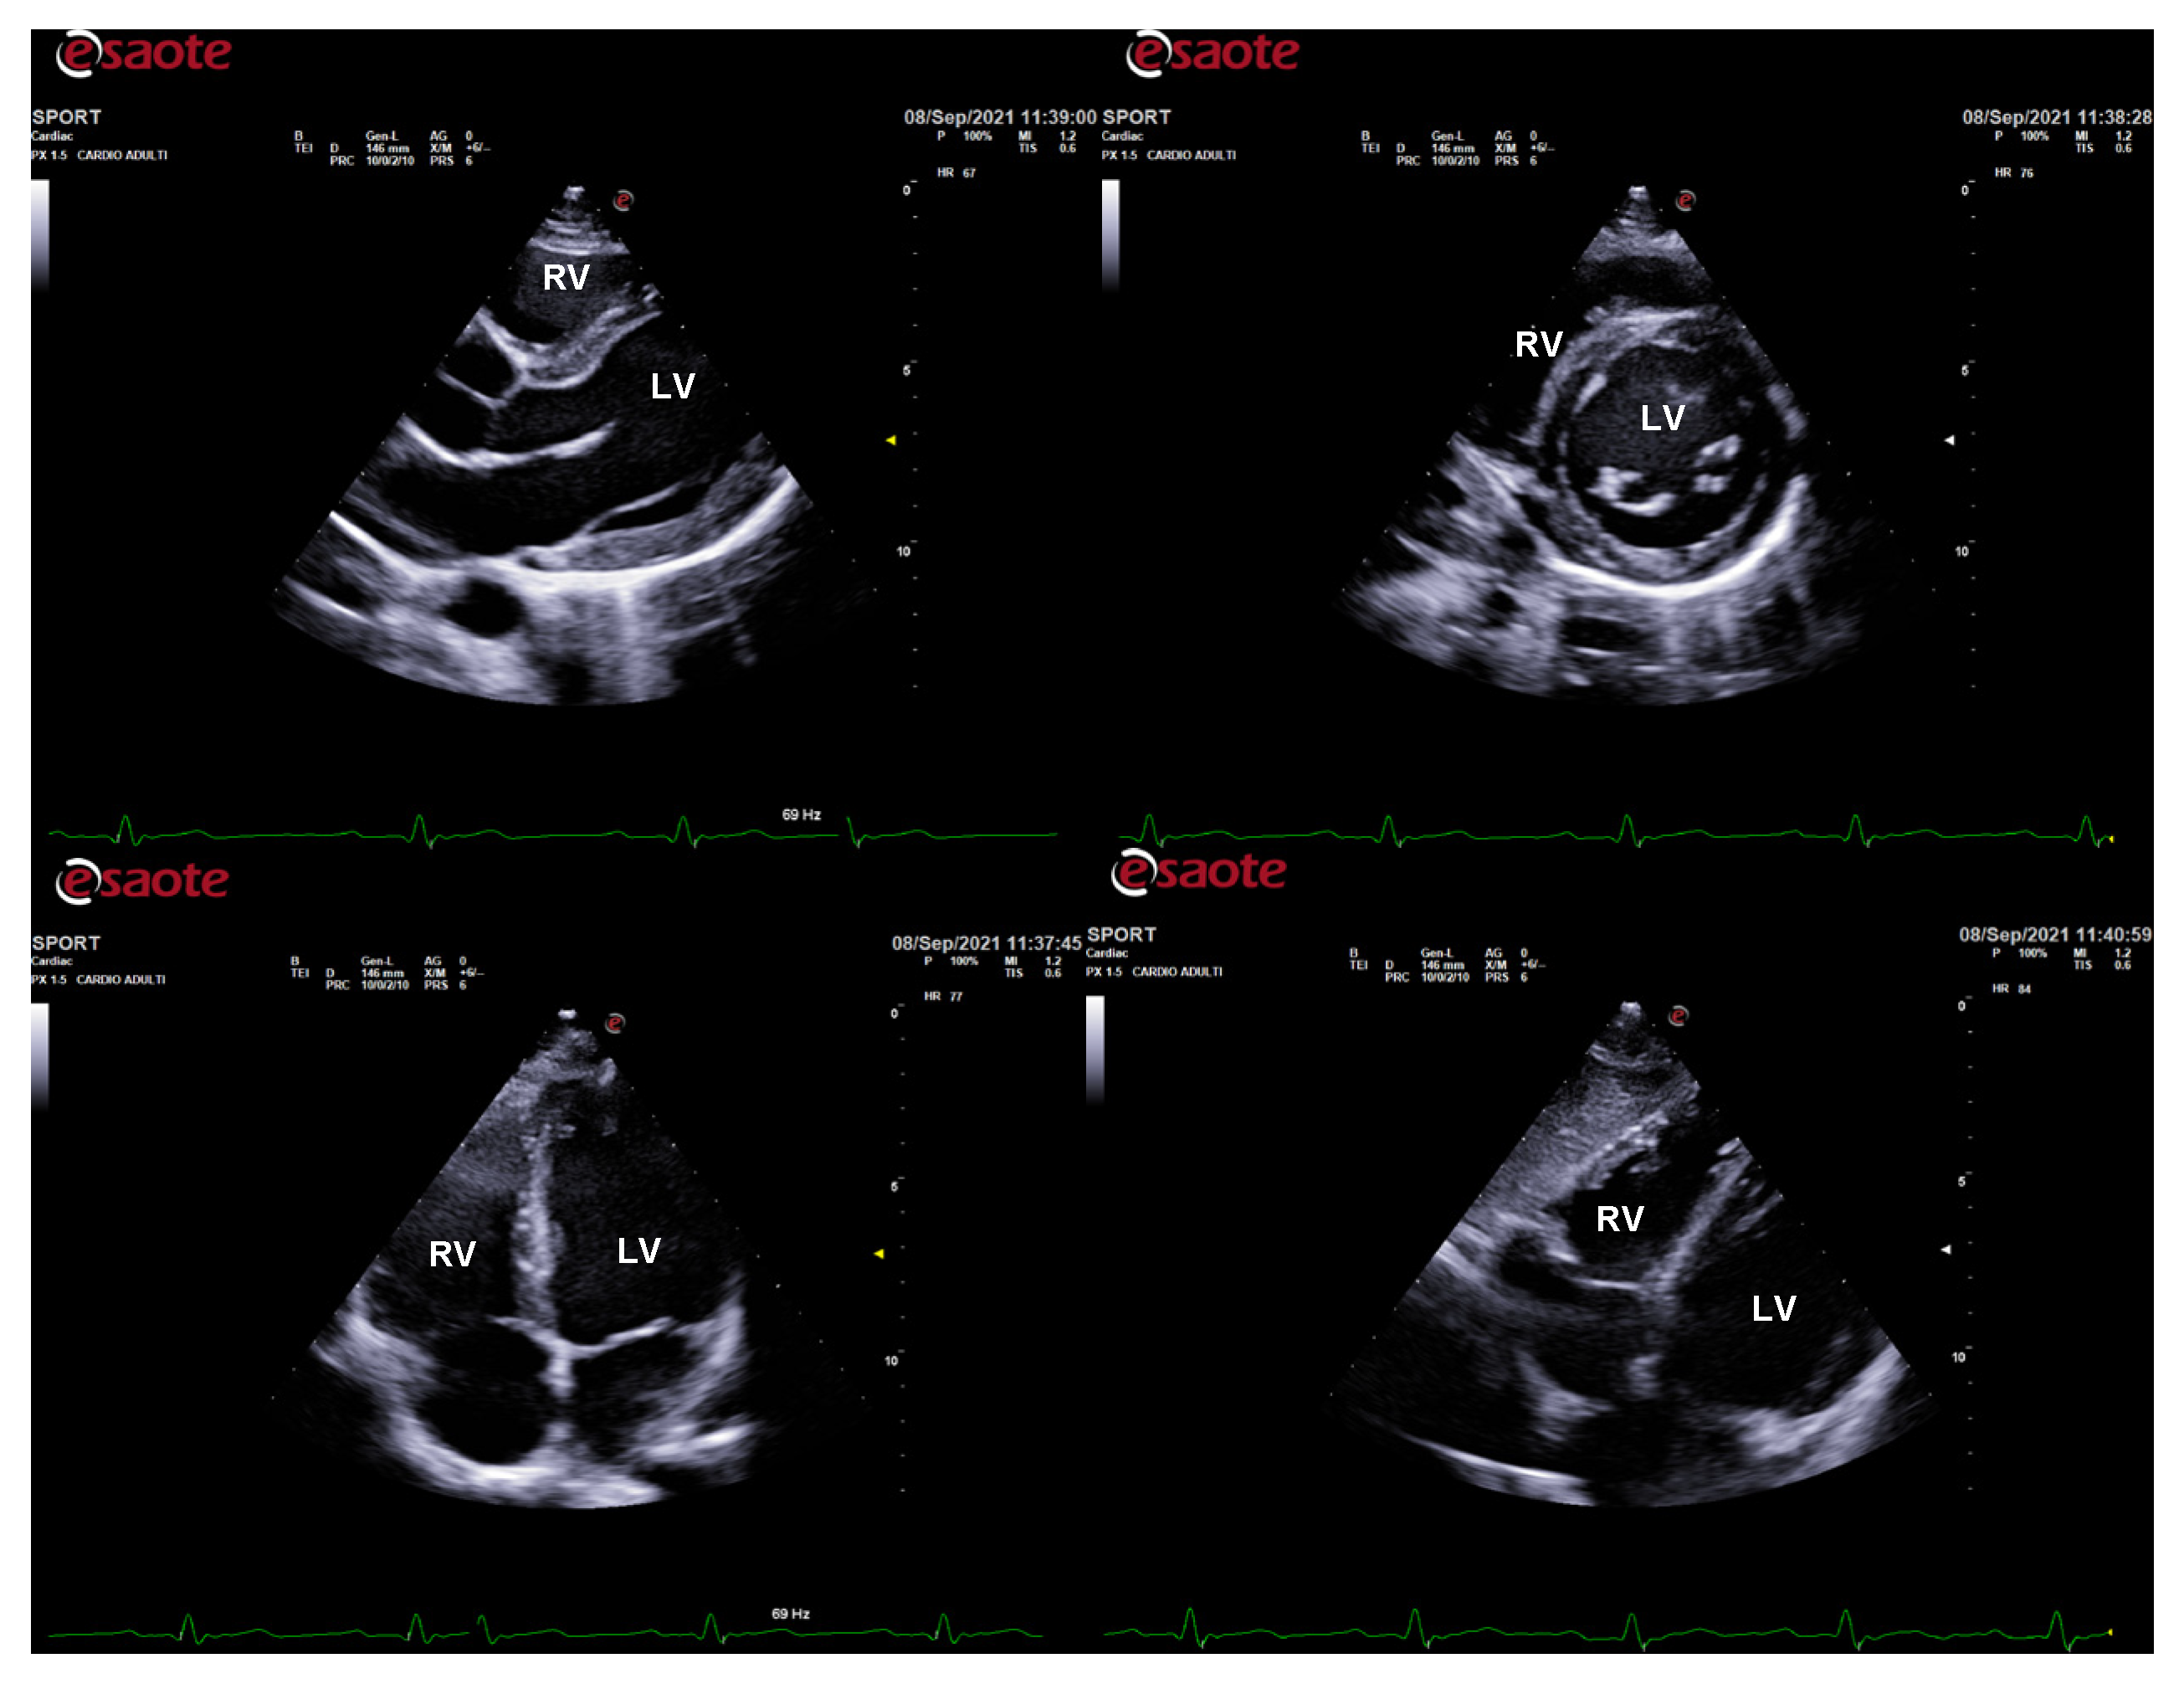

The physiological hypertrophy of athlete’s heart is characterized by a harmonic and symmetric wall thickening that is homogeneously distributed and involves all the cardiac chambers (Figure 1). The exercise-induced chamber thickening is proportional to the type of sport participated (mainly in combined power and endurance disciplines) and it is reversible after temporary (3 months) detraining [10]. A physiological enlargement of both ventricles is usually observed (mostly among endurance athletes), together with a proportional atrial enlargement [11,12,13,14,15,16]. Despite the cardiac chambers’ hypertrophy and enlargement, cardiac systolic function is not altered in athletes, with no significant differences compared to untrained subjects [12,17,18,19]. Likewise, LV diastolic function is normal and an increased contribution of early filling velocity at rest (E/A > 2) can be observed [20,21,22,23,24]. Finally, aortic root diameters are, generally, normal in athletes [25,26,27].

Figure 1.

Standard echocardiography in an endurance athlete (cyclist). The physiological hypertrophy of the athlete’s heart is characterized by harmonic and symmetric wall thickening which is homogeneously distributed and involves all the cardiac chambers. In parasternal long-axis (top left), short-axis (top right), apical 4-chamber (bottom left), and subcostal (bottom right) views, both left and right chamber dilatation is evident. LV: left ventricle; RV: right ventricle.